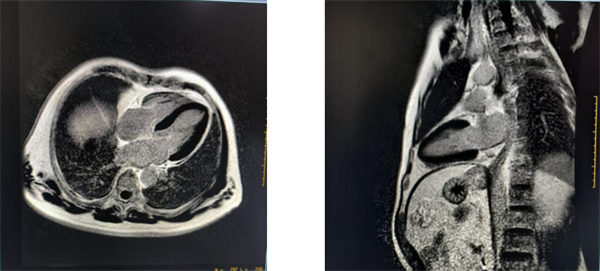

近日,北京中医药大学第二临床医学院(东方医院)放射科成功完成首例心脏磁共振检查,为一名疑似心肌病患者提供了病灶精准定位与组织定性。这标志着东方医院在心血管疾病无创精准诊断领域,具备当前评估心肌病变的无创性影像学“金标准”诊断能力,实现了从传统形态学评估到心肌组织病理特性“可视化”诊断的关键跨越。

心脏结构精妙、动态复杂,其疾病的精准评估一直是临床难点。相较于超声、CT等传统影像手段,心脏磁共振凭借其无辐射、超高软组织分辨率、多参数定量成像的独特优势,可对心脏结构、功能、灌注及组织特征进行 “一站式”全面评估,被誉为当前评估心肌病变的无创性影像学“金标准”。

更精准:犹如为心脏做一次“高清病理切片”,能清晰识别心肌炎症、水肿、纤维化(瘢痕)等CT/超声难以显示的微小病变,实现诊断的“明察秋毫”。

更全面:一次检查,即可同步获取心脏结构、心室功能、瓣膜情况、心肌活性等信息,为心肌炎、心肌病、冠心病、心脏肿瘤、先天性心脏病等复杂疾病的诊断、鉴别与疗效评估,提供决定性的影像学依据。